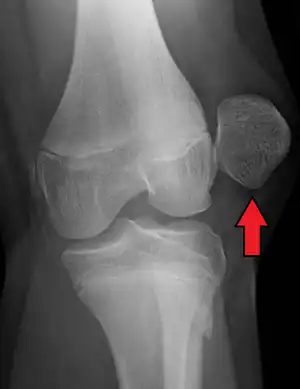

X-ray showing a patellar dislocation, with the patella out to the side. | |

A patellar dislocation is a knee injury in which the patella (kneecap) slips out of its normal position.[5] Often the knee is partly bent, painful and swollen.[1][2] The patella is also often felt and seen out of place.[1] Complications may include a patella fracture or arthritis.[3]

A patellar dislocation typically occurs when the knee is straight and the lower leg is bent outwards when twisting.[1][2] Occasionally it occurs when the knee is bent and the patella is hit.[1] Commonly associated sports include soccer, gymnastics, and ice hockey.[2] Dislocations nearly always occur away from the midline.[2] Diagnosis is typically based on symptoms and supported by X-rays.[2]